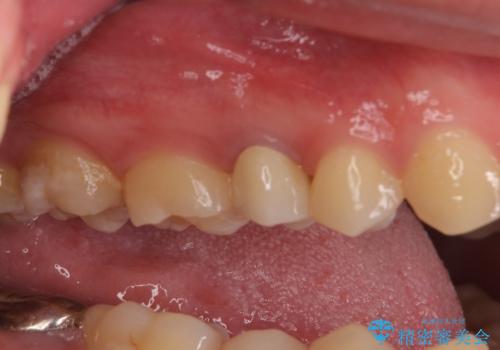

右上の被せものを除去したところ、中で歯が割れていたため、部分矯正で引っ張り出すことになりました。

歯を引っ張り出したり、歯肉の手術の経過待ちの間に、患者様のご希望で他の歯の虫歯治療も行いました。